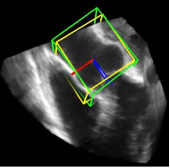

利用2891次心脏超声检查的数据集,Ghesu等结合深度学习和边缘空间学习进行医学图像检测和分割[12]。“大参数空间的有效探索”和在深度网络中实施稀疏性的方法相结合,提高了计算效率,并且与同一组发布的参考方法相比,平均分割误差减少了13.5%,八位患者的检测结果如图4所示。Brosch等人利用MRI图像上研究多发性硬化脑病变分割的问题。开发了一种3D深度卷积编码器网络,它结合了卷积和反卷积[13],图5.增加网络深度对病变的分割性能的影响。卷积网络学习了更高级别的特征,并且反卷积网络预进行像素级别分割。将网络应用于两个公开的数据集和一个临床试验数据集,与5种公开方法进行了比较,展现了最好的方法。Pereira等人的研究中对MRI上的脑肿瘤分割进行了研究,使用更深层的架构,数据归一化和数据增强技巧[14]。将不同的CNN架构用于肿瘤,该方法分别对疑似肿瘤的图像增强和核心区域进行分割。在2013年的公共挑战数据集上获得了最高成绩。

图4示例图像显示了不同患者的检测结果从测试集。检测到的边界框以绿色显示,标准的框以黄色显示。原点位于每个框中心的线段定义相应的坐标系